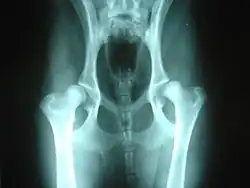

Hip dysplasia may be helped by hydrotherapy.

A number of conditions in dogs may be aggravated by or may show slow or no improvement as a result of weight bearing exercise. Among these are hip dysplasia and osteochondritis dissecans (OCD), conditions most common in medium to large purebred dogs, such as German Shepherds, Labrador Retrievers or Golden Retrievers; chronic degenerative radiculomyelopathy (CDRM), a degenerative disease of the spinal cord which causes hind limb problems in German Shepherds; and luxating patella which is seen predominantly in small and toy breeds.[2]